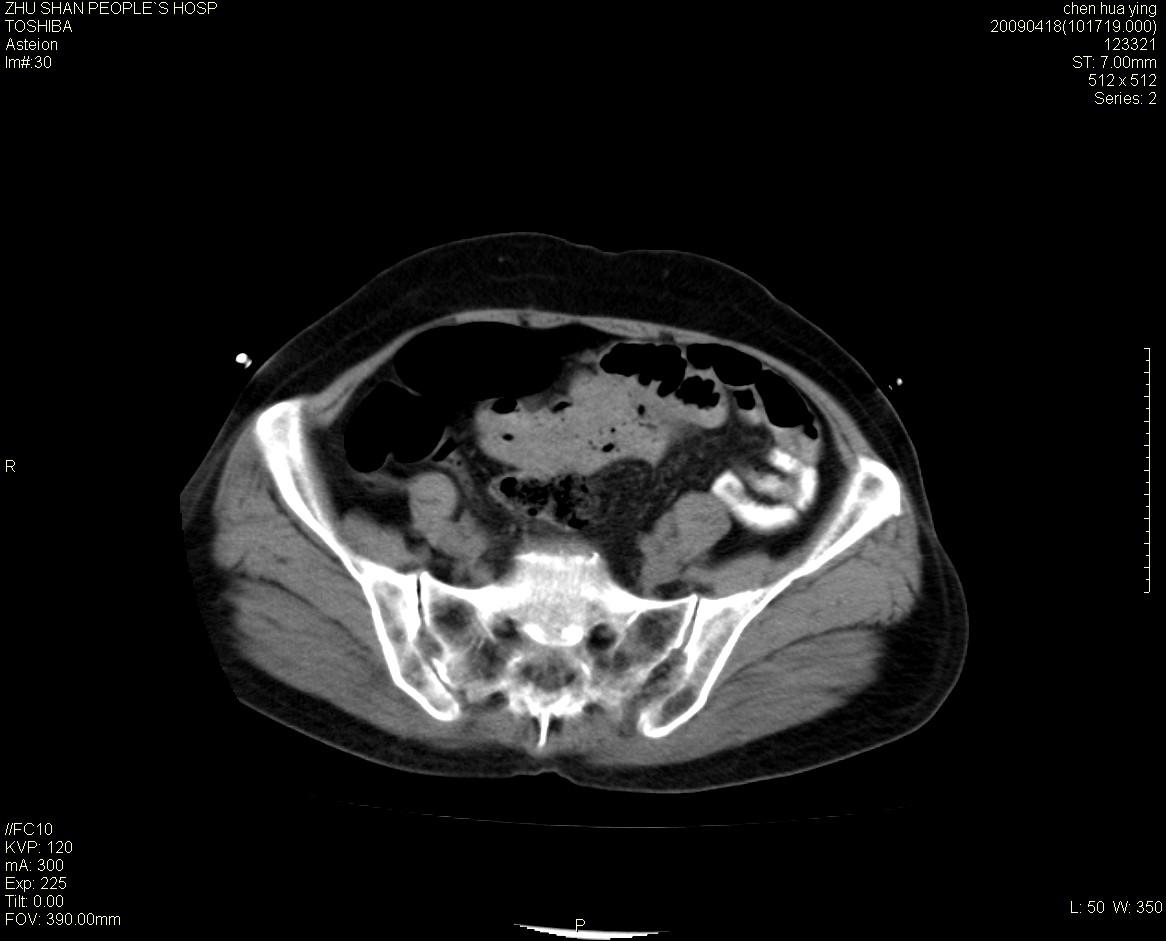

女性病人 65岁 腹部包块半年余结肠造影未见异常.

病灶略呈圆形有分叶状,上部层面呈实性,右侧见圆形低密度区,灶内见团块状钙化,病灶下方与肠管分境不清,考虑间质瘤可能性大,建议肠道准备后增强